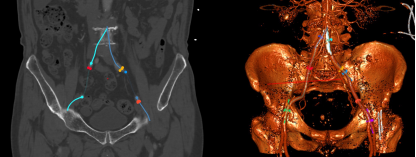

入路状况

结构上,该病例为Type0型二叶瓣,瓣叶钙化、增厚严重,且流出道呈喇叭口型。考虑远期效果,为避免瓣膜选择过大打开不良造成瓣膜过早衰败,可参照瓣上狭窄结构Downsize选择TAV24瓣膜;同时为了避免瓣膜移位及瓣周漏,应采取高位定位释放的策略,释放过程中应留意输送系统及导丝的牵拉稳定瓣膜位置,如遇瓣膜位置不佳,及时应用可回收功能进行再次定位释放。双侧入路直径充足,但双侧股动脉分叉均较高,可考虑主入路外科切开后于稍高处穿刺。

全麻下,以右侧股动脉为主入路(外科切开后穿刺),使用22mm球囊预扩张,植入TAV24型号Vitaflow瓣膜。